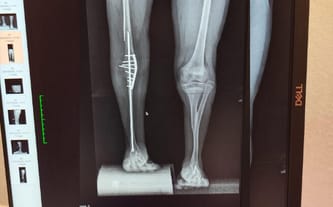

wrodzony obustronny brak kości piszczelowych